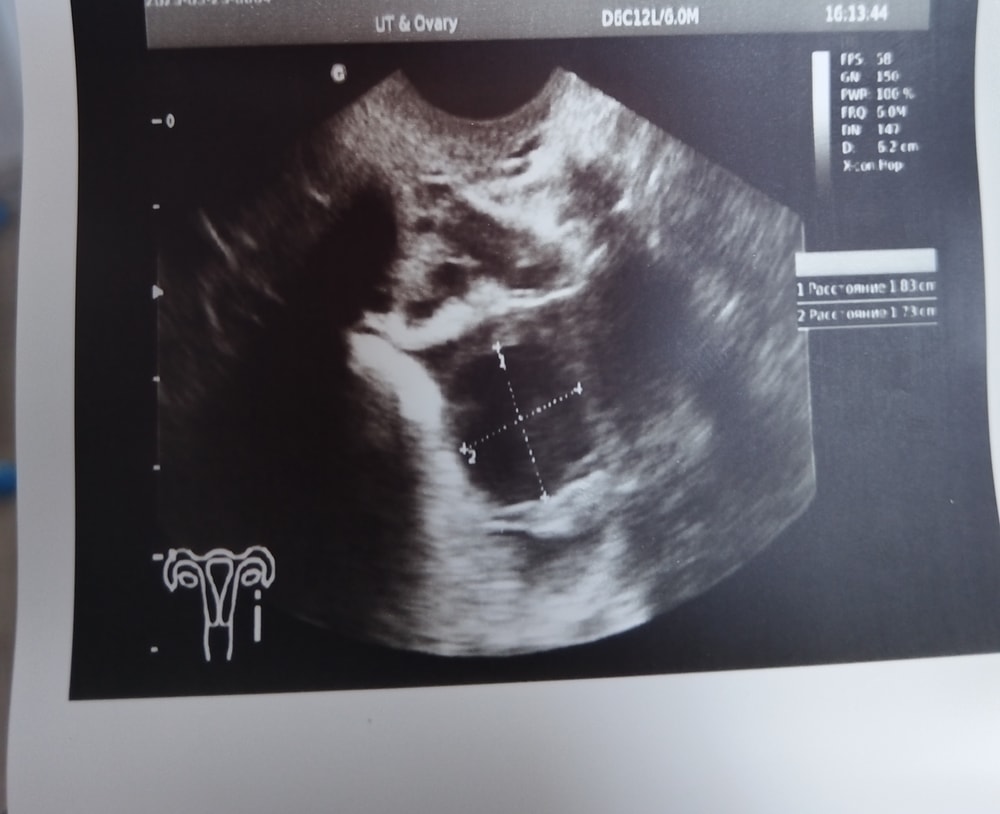

Как то странно он фолликул измерял🤔. У меня двойная была, по этому указано 2 размера. А у вас он и вдоль и поперёк зачем-то измерил... Но судя по его записям доминантный фолликул у Вас 18,3 мм, овуляция может быть от 19 мм, т.е. начиная с сегодняшнего дня и ближайшие 2-3 дня. У всех организмы разные, по этому точно сказать нельзя когда будет овуляция. Фолликул в день прибавляет от 1 до 2 мм. Изображение

Маруся Марусина, в заключение он вообще в левом написал образование 10х11мм и все. Ни описание ни жт ни дф. Вообще ничего не понимаю.

Татьяна, сходите к другому узисту. Т.к. на снимке чёткие размеры и по ним фалликул 18,3мм, а что и откуда он взял 10×11 не понятно, т.к. фолликул так не измеряют.